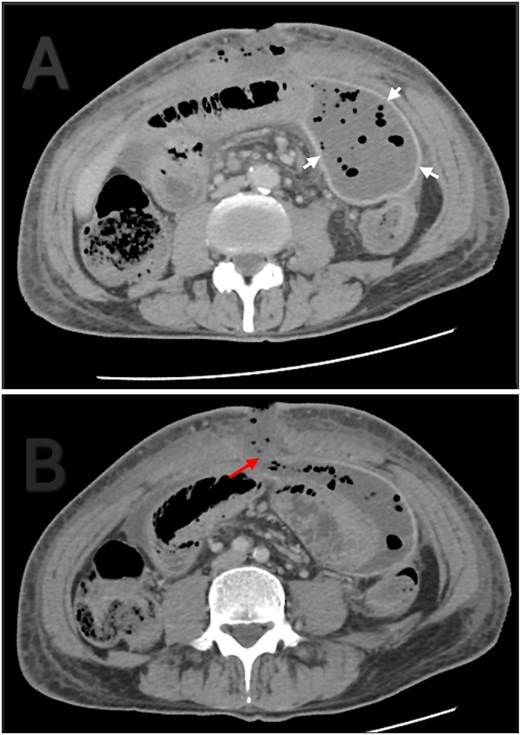

A 56-year-old male patient presented to the emergency department with generalized abdominal pain, obstipation, and vomiting for six days. On examination, there was diffuse generalized abdominal tenderness and a palpable mass in the hypogastric region. Contrast enhanced abdominal computed tomography (CT) revealed clustered ileal loops in the pelvis with multiple transitional zones and dilated proximal small bowel loops (Fig. 1).

Axial (A) and coronal (B) contrast enhanced abdominal CT. Ileal loops congregated at the pelvis (red arrow). Small bowel loops dilation (white arrow).